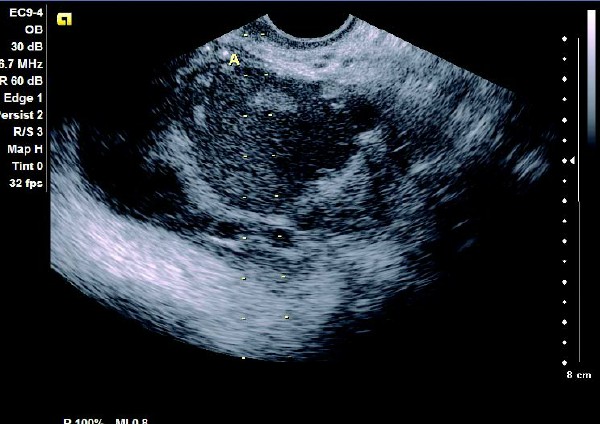

(1)单侧或双侧卵巢内显现椭圆形或圆形无回声暗区,其内充满弱回声光点,囊肿直径一般为5~6 cm,大于10 cm 的较少见。

(2)壁较厚,囊内充满细小均匀点状回声,后方回声增强。

(3)常与周围组织有粘连,边界清晰。

患者,女,35岁。每次月经量少,痛经,近来行经期延长、疼痛加重来院诊治。超声报告显示子宫前倾位,子宫体大小为:5.9cm×5.1cm×4.8cm,形态规则,边界清晰,宫避回声匀称,宫腔线居中,内膜厚度0.6cm,宫内未见异常回声。右侧卵巢内可见大小约5.2 cm×4.9cm的无回声区暗区,壁厚,内壁欠光滑,内见密集细光点,边界清晰。CDFI探测囊壁及囊腔内无血流信号。

超声提示:右侧卵巢巧克力囊肿